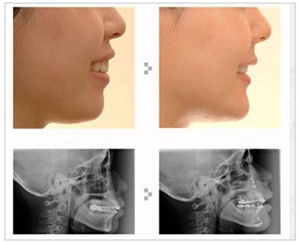

돌출입은 악교정술을 통해 개선할 수 있다. 돌출입 수술을 하면 웃을 때 잇몸이 드러나는 것을 개선하면서 다방면으로 이미지 개선효과를 볼 수 있다. 돌출된 입에 비해 무턱 같던 턱도 적당히 나오고 낮아 보이던 코도 높아 보이는 장점이 있다.